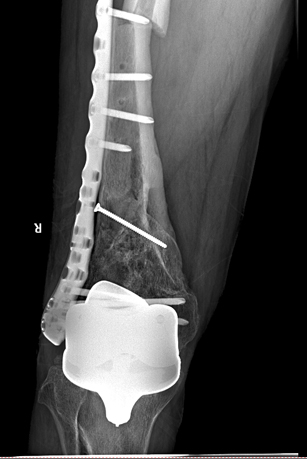

术后影像

在手术之前,首先做股骨全长薄层扫描CT,将患者股骨影像及数据搜集并记录下来,通过3D打印技术制作出一个1:1比例的股骨“复制品”,它的直径、长短、髓腔形态都与患者真实情况完全相符,甚至患者骨骼上每一块凹陷与凸起,每一点纹理和痕迹都呈现得一清二楚。然后通过在体外对模型进行模拟手术操作,准确制订出了髓内钉的入针点、长度、直径,精确计划出远端锁钉准确位置。手术时,按着术前的设计顺利完成了手术,大大缩短了手术时间,减少了对患者的创伤。术后影像骨折解剖复位,锁钉位置精准无误,术后患者顺利康复。